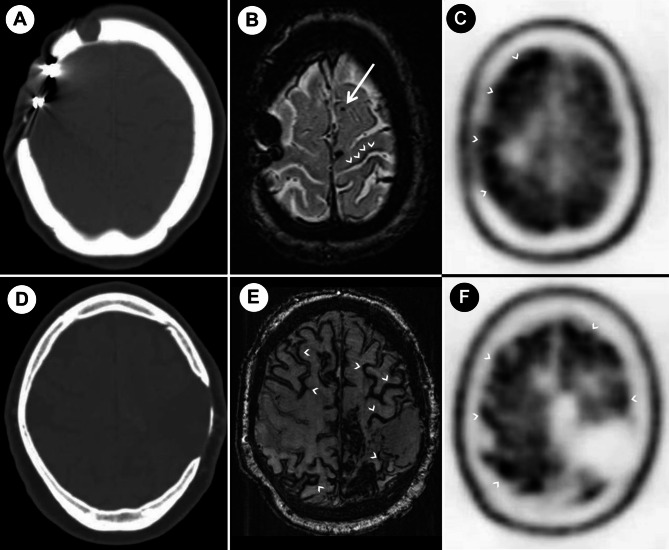

对医源性脑淀粉样血管病(iCAA)的认识正在增加,但其病理生理尚不清楚。我们讨论了两个以前未发表的可能的iCAA病例的临床、影像学和神经病理学结果的意义:一名55岁女性,表现为快速进行性认知障碍,显示CAA的影像学和组织学证据,并在6岁时接受了神经外科治疗;1例56岁男性,5岁时有四年复发性脑出血史,并接受过神经外科手术治疗。在第一个病例中,进行了脑活检。此外,对具有神经病理资料的iCAA病例的系统回顾表明,大多数患者伴有淀粉样蛋白实质沉积,没有或只有少量tau病理。tau病理在iCAA中的病理生理作用尚不清楚。iCAA患者表现为认知障碍而无症状性脑出血可能被误诊。

Awareness concerning iatrogenic cerebral amyloid angiopathy (iCAA) is increasing but its pathophysiology remains unclear. We discuss the implications of the clinical, imaging and neuropathological findings in two previously unpublished cases of probable iCAA: a 55-year-old female presenting with rapidly progressive cognitive impairment, showing imaging and histological evidence of CAA and having undergone neurosurgical treatment at the age of 6; and a 56-year-old male with a four-year history of recurring intracerebral hemorrhages (ICH) and neurosurgical intervention at the age of 5. In the first case, a brain biopsy was performed.Additionally, a systematic review of iCAA cases with neuropathological data suggests that most of the patients have concomitant amyloid parenchymal deposition and none or minimal tau pathology. The pathophysiological role of tau pathology in iCAA remains unclear. iCAA patients presenting with cognitive impairment without symptomatic ICH may be underdiagnosed.